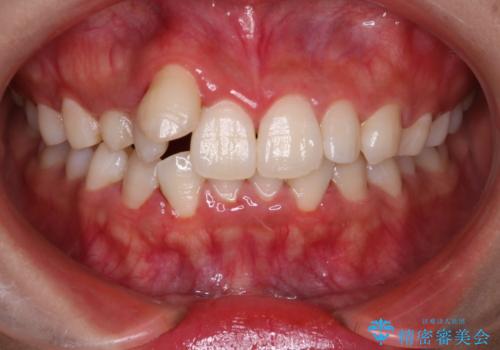

【インビザライン】八重歯が気になる

- 乳歯を抜歯してスペースを確保し八重歯の改善を行いました。

インビザラインをしっかり使用していただいたので、きれいな歯並びになりました。